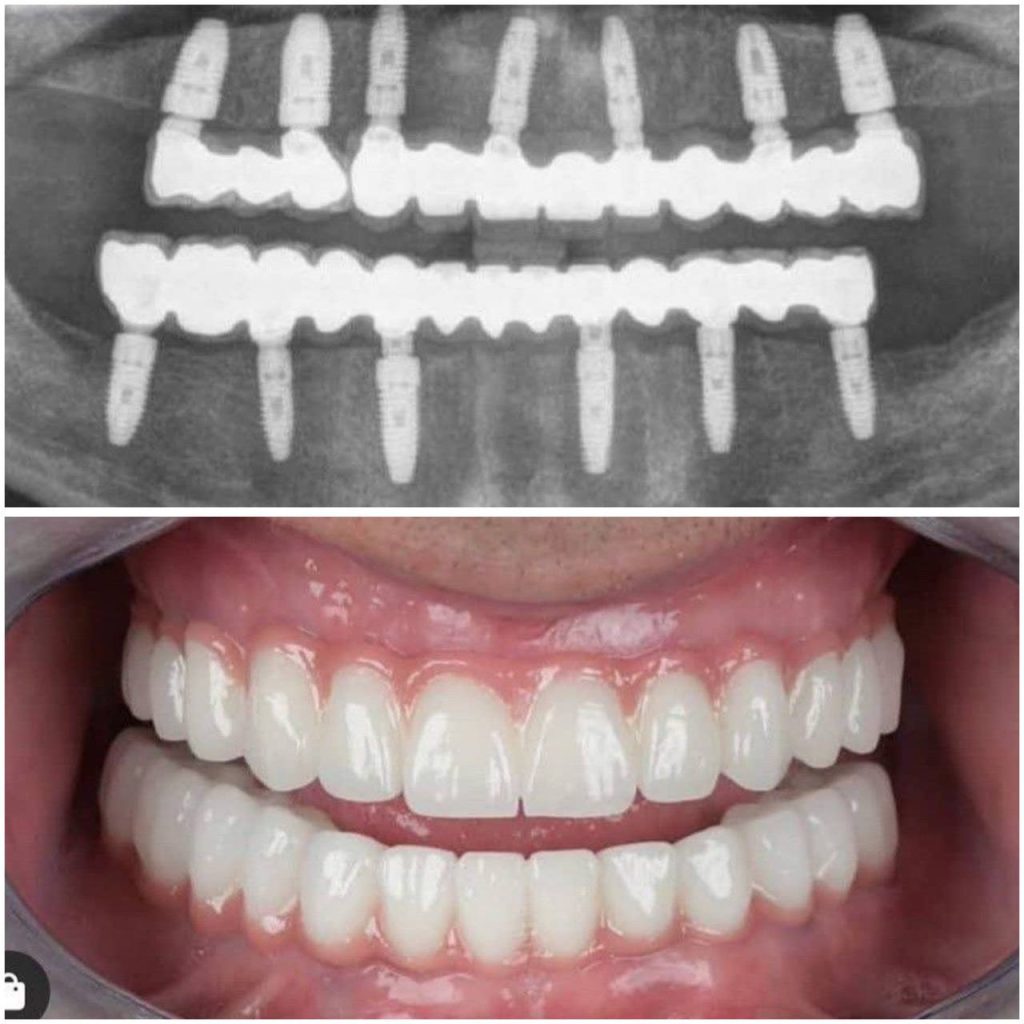

имплантация All-on-6 (Все на 6)

Имплантация All-on-6 позволяет восстановить красивую, функциональную улыбку даже при полном отсутствии зубов или их сильном разрушении. Имплантация Все на 6 (All-on-6 ) в нашей клинике в Москве проводится по современным протоколам с точным планированием и контролем на каждом этапе.

Что такое All-on-6?

Технология «Все на 6» предполагает установку:

- 6 имплантов в костную ткань;

- фиксацию несъёмного протеза на них.

Импланты равномерно распределяют жевательную нагрузку, обеспечивая надёжную фиксацию и долговечность конструкции.